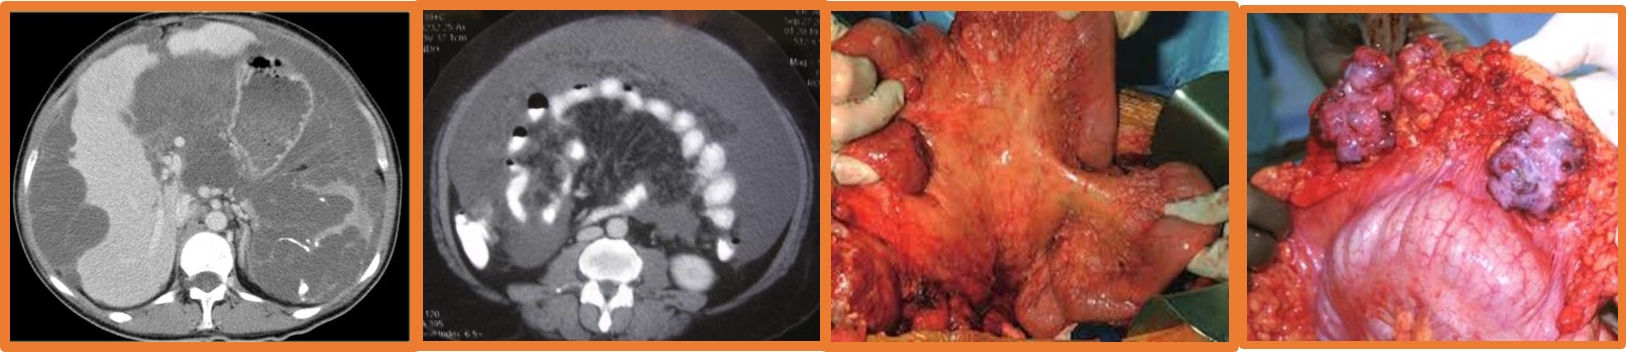

- Mesothelioma

- Rare

- Exposure to asbestos

- Poor prognosis

- Abdominal pain, wt. loss. mass

- US, CT

- Debulking surgery,

- Chemo/radiotherapy

Carcinomatosis peritonei: Terminal event, studded with secondary growth, ascites (straw, blood stained).